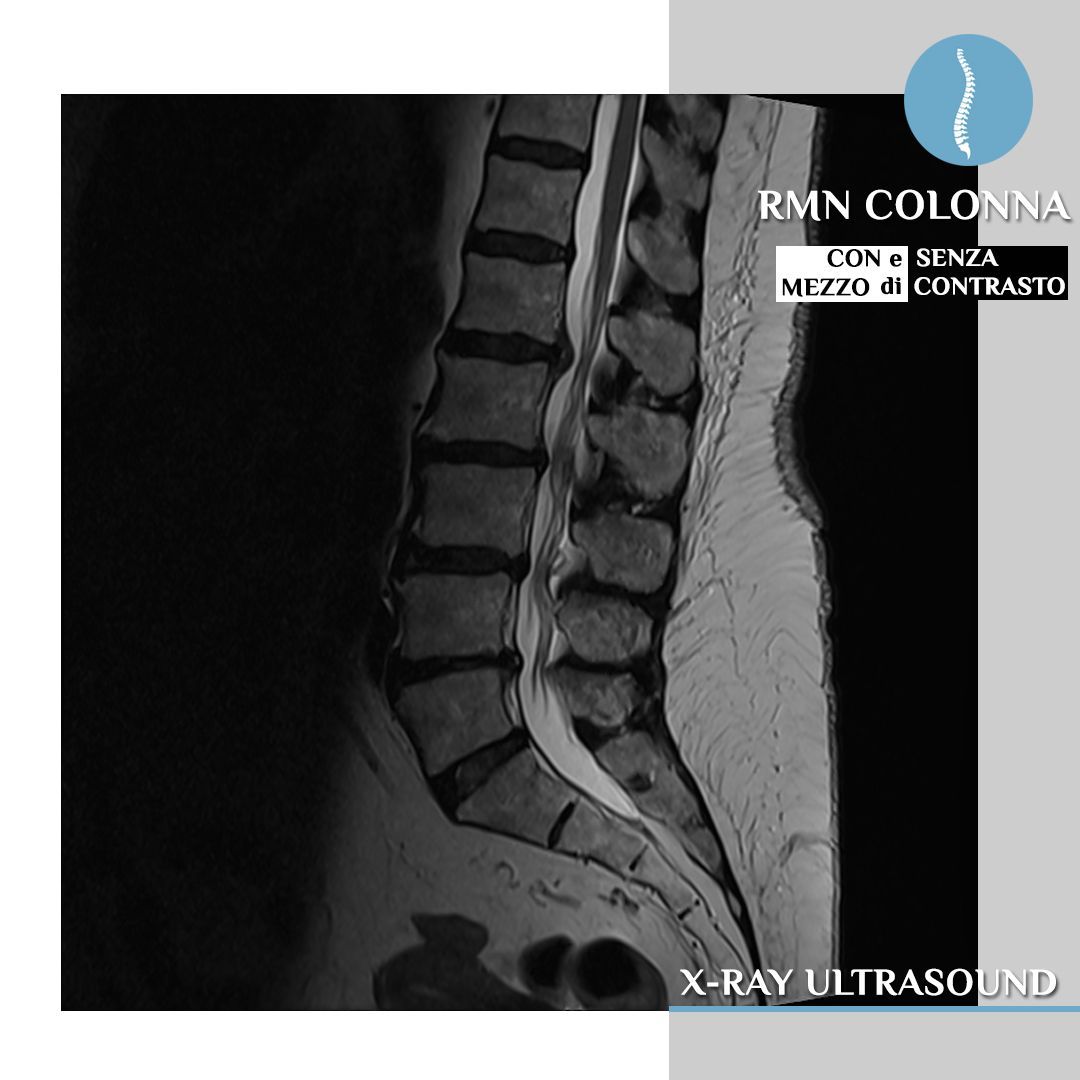

Diagnosi di patologie complesse: la risonanza Magnetom Altea è particolarmente indicata per la diagnosi di patologie complesse di diverse aree del corpo, tra cui:

- Colonna vertebrale: vertebre, dischi intervertebrali, midollo spinale